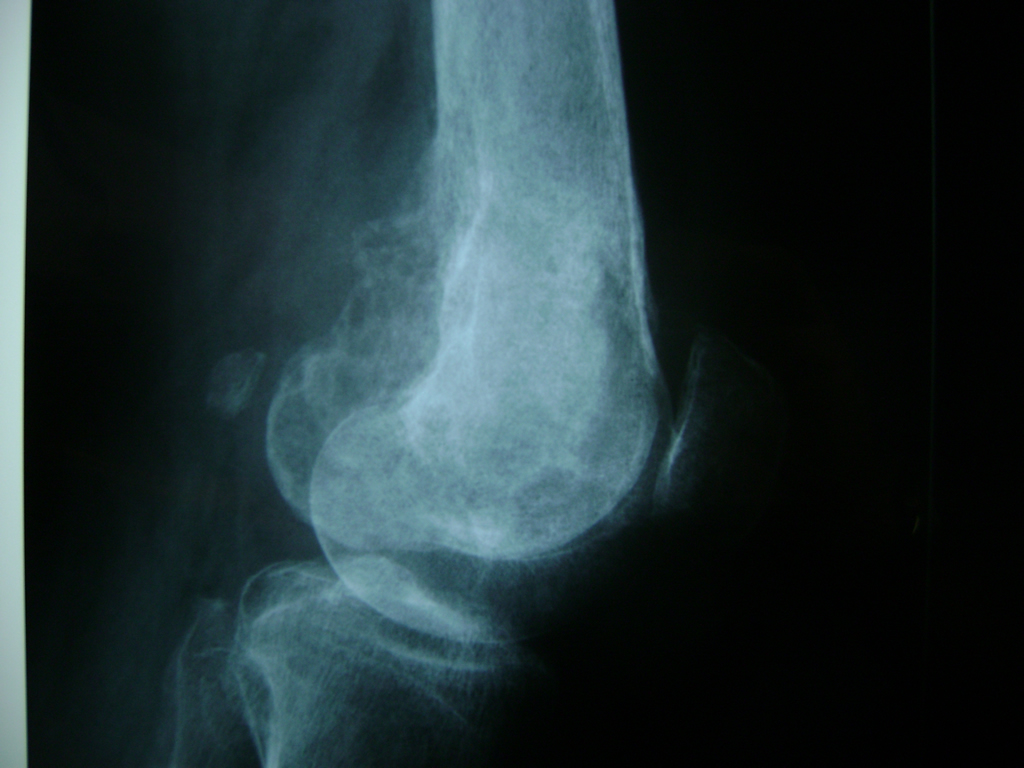

Cirugias en El Salvador - Rodilla

La artroscopia de rodilla es un cirugía en el cual la estructura interna de la articulación es examinada ya sea para realizar un diagnostico o para realizar un tratamiento, este procedimiento se realiza utilizando un instrumento parecido a un pequeño tubo llamado artroscopio.